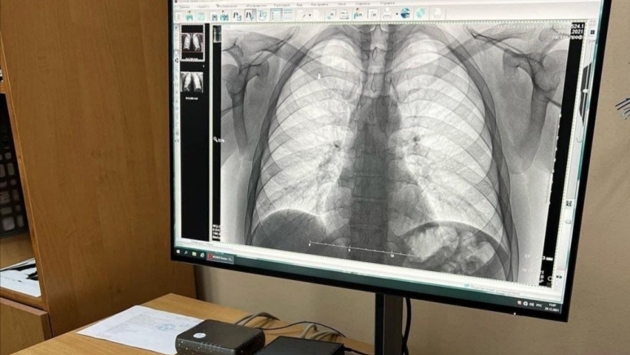

Забайкальцев приглашают пройти обследование на раннее выявление заболеваний легких в преддверии Дня борьбы с туберкулезом